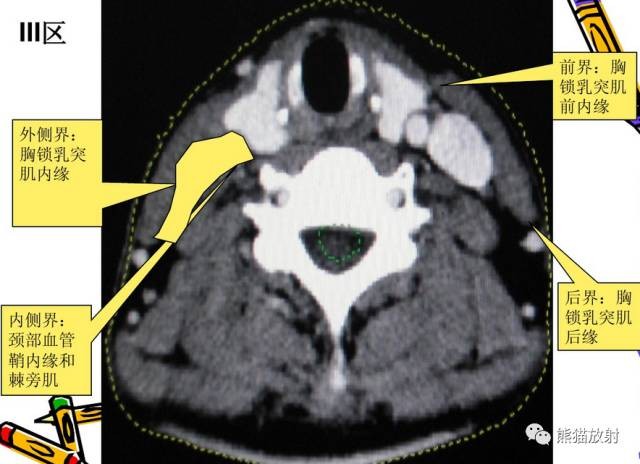

III区:颈内静脉链中组

舌骨水平CT增强图像

横白线划在胸锁乳突肌后缘。

白线前为III区淋巴结,后为V区淋巴结。